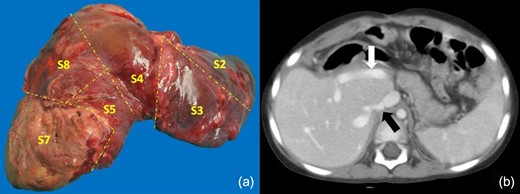

The patient was then scheduled for the second stage on POD 16. Abdominal cavity exploration and adhesiolysis were performed without difficulty. Segment 7 showed necrosis and no purulent fluid was recovered. The left and right anterior branches of the portal vein, as well as the glissonean s7 pedicle were clipped, stitched and divided, including the hepatic veins. The outflow of s6 remained patent through the right inferior hepatic vein which was spared. A left trisectionectomy extended to s7 with s1 resection (Fig. 2a) was performed. 200cc of red blood cells were transfused. Operative time was 200 minutes.

(a) Gross pathologic specimen after left trisectionectomy extended to s7. The tumor invades all segments resected, viable tumor was found in the microscopic study. (b) Last CT scan control is shown, with no evidence of recurrence in the liver remnant nor signs of portal hypertension. The white arrow shows the posterior portal branch and s6 pedicle. The black arrow points at the IRHV.

The patient’s postoperative recovery showed no signs of liver failure. On POD 6 of the second stage she was medically treated for pneumonia that resolved without incident; she was discharged on POD 30. The pathologic examination of the surgical specimen revealed epithelial-type hepatoblastoma with 70% necrosis, and surgical margins free of disease (R0 resection).

The liver volume on December 2015 was 453cc (Fig. 2b). After three cycles of post-operative adjuvant chemotherapy, the AFP levels remained within normal range (<7 ng/ml). A follow-up control performed on November 17, 2018 continued to be without evidence of disease (AFP levels 1.56 ng/ml). Clinical and laboratory parameters showed normal liver function. The BMI-for-age was at the 85th percentile.